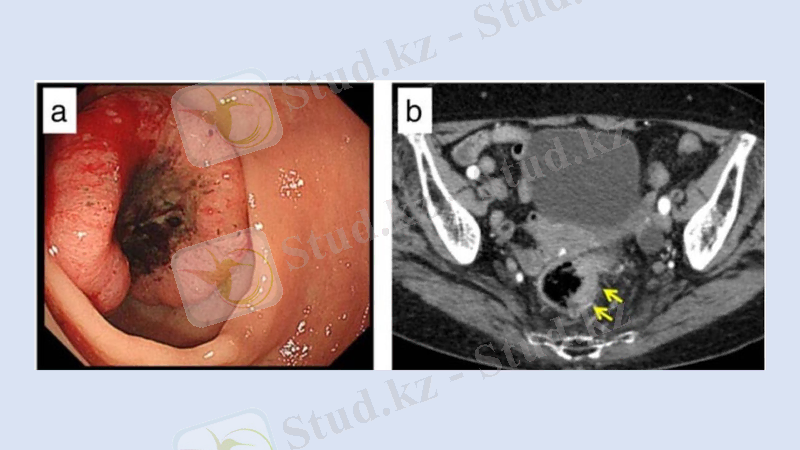

Тік ішек рагын анықтау тәсілдері

Анамнезді жан-жақты жинау;

Саусақпен қарау және бимонуалды жағдайда әйелдердің қынабын тексеру;

Ректороманоскония;

УДЗ;